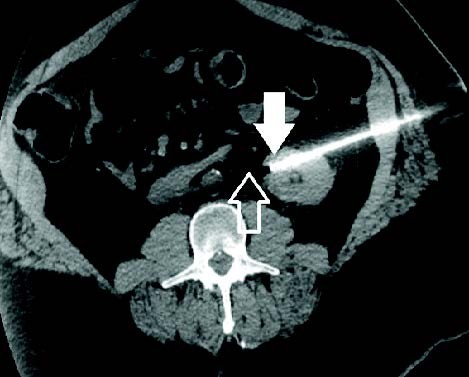

MRI image from Chary cryoneurolysis case MRI image from Chary cryoneurolysis case

Celiac Plexus Cryoneurolysis case study

A 66-year-old man presented with intractable upper abdominal pain refractory to medical management with opiates. MRI axial images through the celiac plexus at the celiac plexus at the level of the celiac axis and SMA origins demonstrate bulky retroperitoneal adenopathy and soft tissue tumor infiltrate. Two IceRod™ 1.5 CX needles were placed within and along the bilateral celiac plexus via CT-guidance. The CT Axial image (right) in prone position shows right-sided iceball formation along the celiac plexus demonstrating excellent coverage. The patient reported pain at 2/10 after a 3-day follow-up pain assessment; the pain score before the procedure was a 10/10.

Aron Chary, MD I MidSouth Imaging - Vascular Interventional Physicians I Memphis, TN